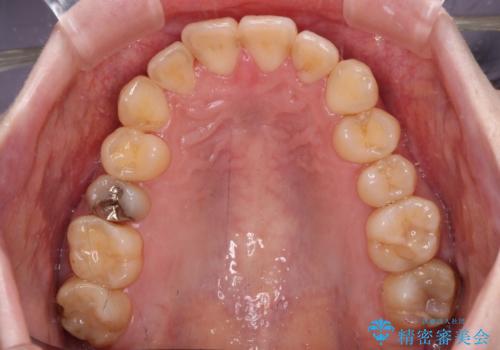

デコボコ歯列をきれいに インビザラインによる矯正治療

- 上下歯列全体のデコボコを気にして来院された患者様です。

主に下顎歯列全体の後方移動とIPR(歯と歯の間を削る)によってデコボコが解消するように設計し、インビザラインにより治療を行うこととしました。